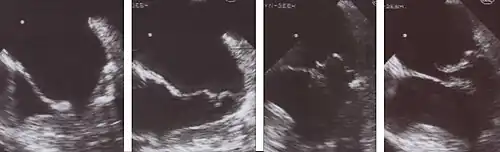

1 Diastole: Beide Mitralsegel weit geöffnet

2 Frühe Systole: Beginnender Klappenschluss

3 Das posteriore Segel prolabiert in den linken Vorhof

4 Beginn der Klappenöffnung